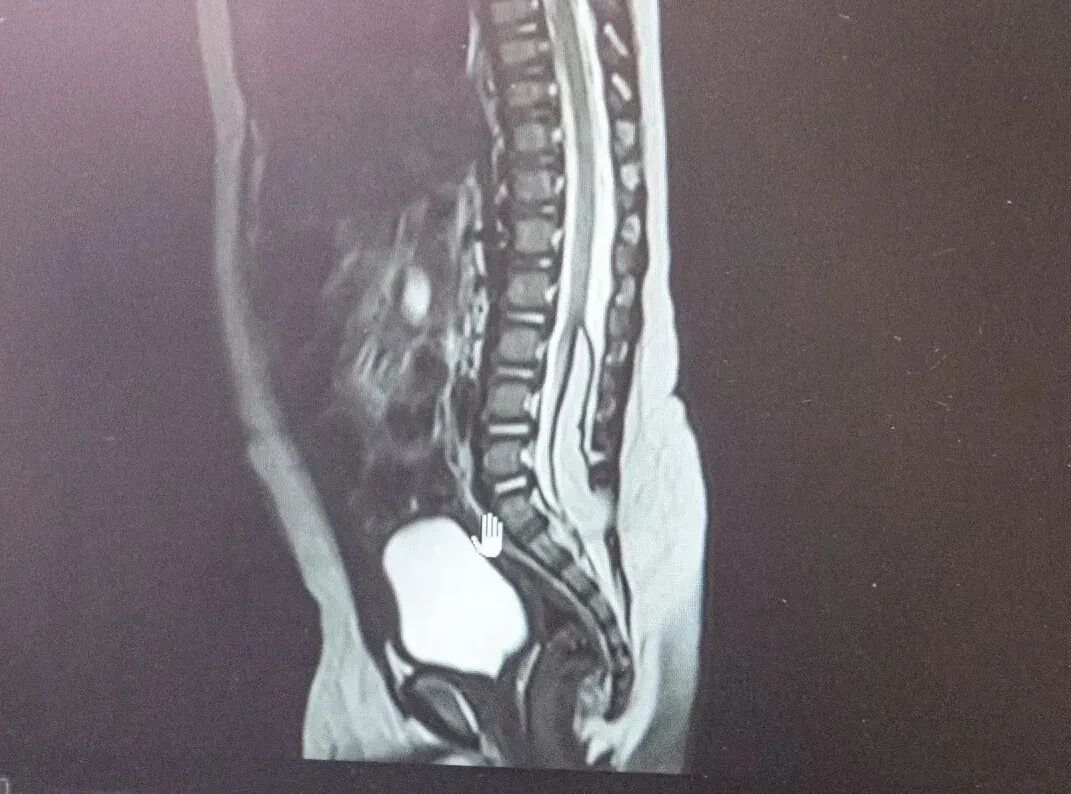

В Кузбасской областной детской клинической больнице имени Ю.А. Атаманова с начала года спасли двух малышей с пороками развития центральной нервной системы. Речь идет о пациентах в возрасте 6 и 8 месяцев, у которых врачи выявили липомиелоцеле.

Как рассказали в министерстве здравоохранения Кузбасса, это редкая аномалия, при которой патологическая жировая ткань формируется в спинном мозге, фиксируя его. В результате спинной мозг не может нормально расти и развиваться вместе с ребенком. Это может обернуться тяжелыми последствиями: нарушением работы тазовых органов и недержанию.

Фото: Министерство здравоохранения Кузбасса